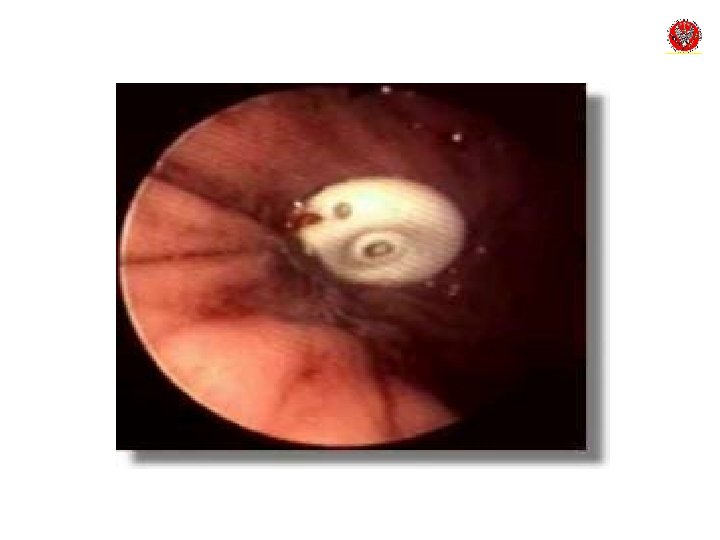

Podstawowe warunki do wykonania PEG • Prawidłowa transiluminacja • Widoczny ucisk powłoki jamy brzusznej na ścianę żołądka • Widoczna igła w świetle żołądka • Brak cech krwawienia

PEG